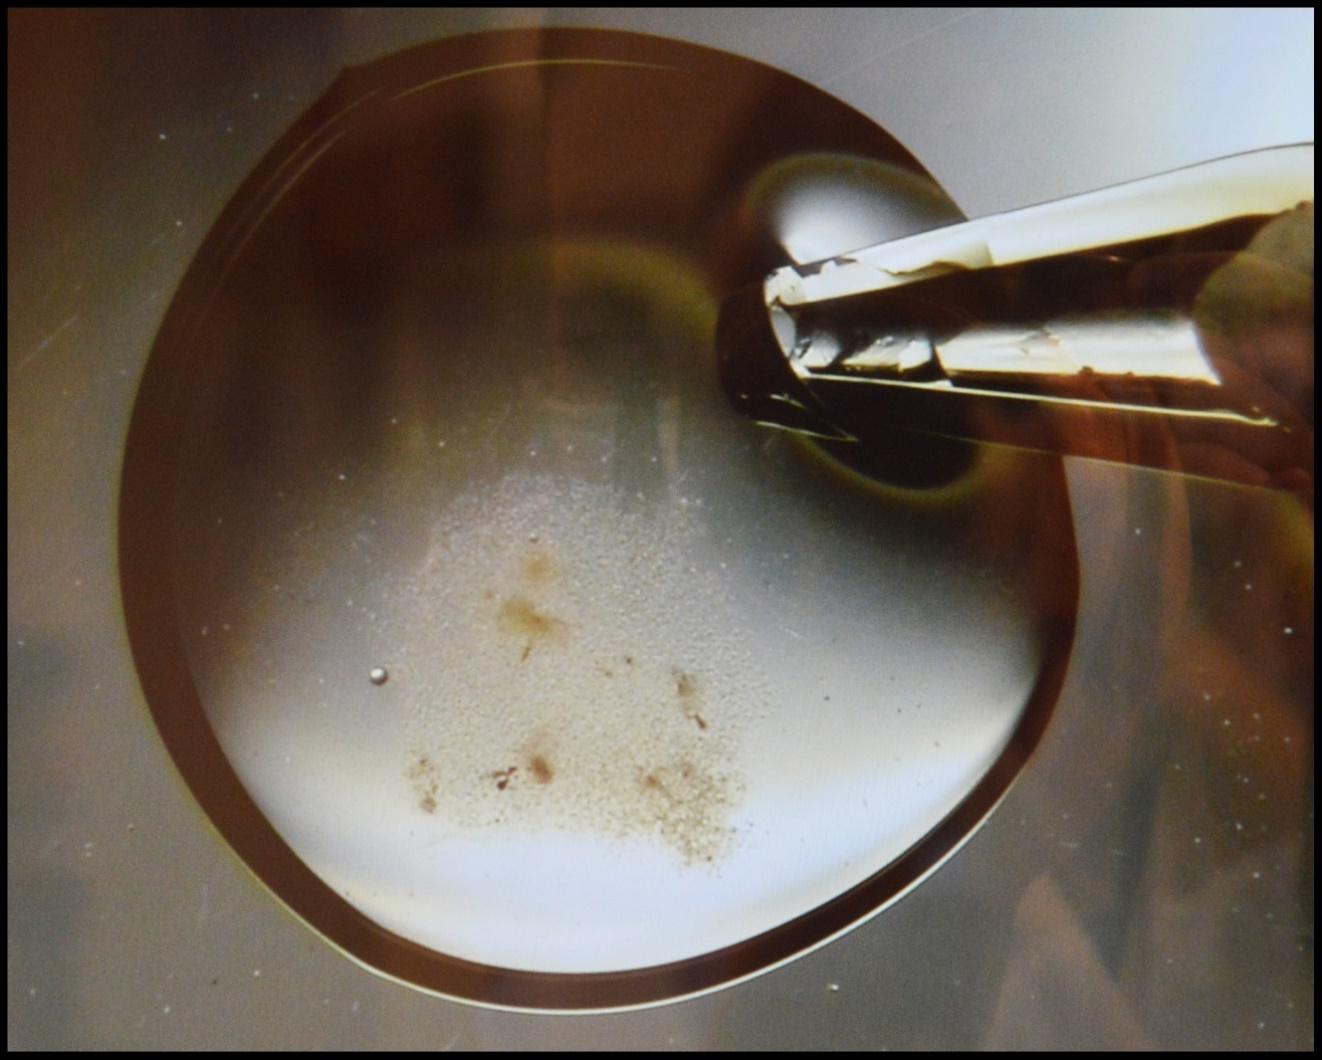

Figuur 2. Analist voegt zaadcellen toe aan de eicel in het petrischaaltje.

Figuur 3. Zaadcellen worden toegevoegd aan de eicel in het petrischaaltje.